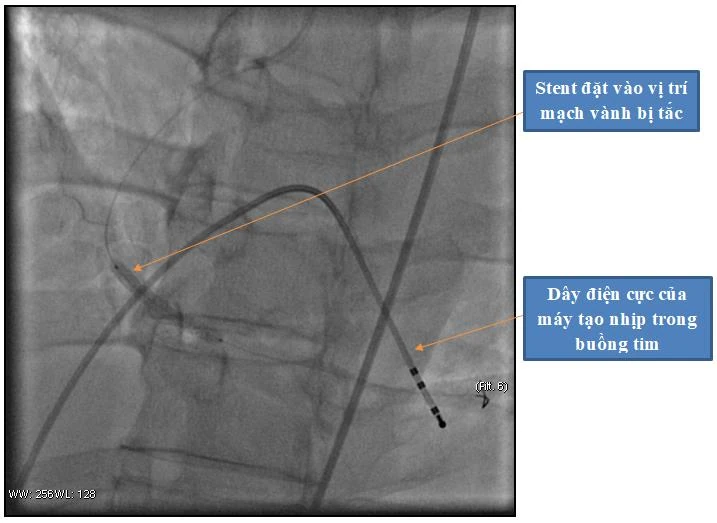

Hình ảnh đặt stent và máy tạo nhịp tim cho người bệnh

Người bệnh nhanh chóng được chuyển vào phòng can thiệp tim mạch để chụp và can thiệp mạch vành tái thông mạch vành bị tắc. Kết quả cho thấy động mạch vành phải bị tắc hoàn toàn. Ekip can thiệp đã tiến hành đặt máy tạo nhịp tim cho người bệnh và đặt 1 stent vào vị trí bị tắc nhằm tái thông động mạch vành.